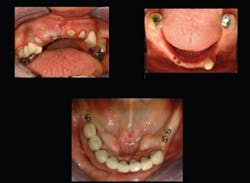

3) Removable partial dentures. In my opinion, this indication is far underused. Most conventional removable partial dentures (RPDs) are not highly successful. Many patients do not use their partials on a routine basis. Mesial or distal to remaining teeth in a partially edentulous mouth is almost always a triangle of bone into which either an SDI or a smaller conventional-diameter implant can be placed (Fig. 6). In many cases, placement of SDIs in this remaining triangle of bone, with or without a flap, is highly successful and predictable. Many uses for SDIs are present for removable partial dentures (Figs. 7 and 8).

Fig. 6: Mesial and distal to remaining teeth is almost always a triangle of dense bone into which an implant can be placed.